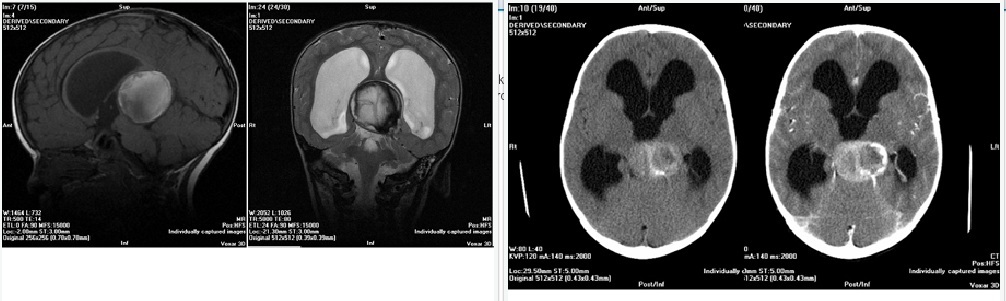

Seorang anak laki-laki datang dengan riwayat “dysequilibrium” sebelah kanan sejak 2 minggu lalu dan gangguan cara berjalan. pada pemeriksaan terdapat gangguan pada refleks muntah. Manakah dibawah ini yang paling sering berhubungan dengan kondisi patologis tersebut?

Diffuse pontine gliomas classically present with cerebellar signs, lower cranial nerve deficits, and motor/sensory changes. Signs of CSF obstruction are more uncommon in this brainstem glioma subtype. Fibrillary astrocytoma is the most common histological type; although the genetic profile of mutations is varied, frequently TP53 and loss of 22q heterozygosity are encountered. The Ki-67 index is usually not elevated. Perivascular pseudorosettes are commonly seen in ependymomas and may also been seen in neurocytomas, PNETs and medulloblastomas. Loss of heterozygosity of chromosome 1p/19q is most commonly seen in oligoastrocytomas. INI-1 mutations are associated with atypical rhabdoid tumors.